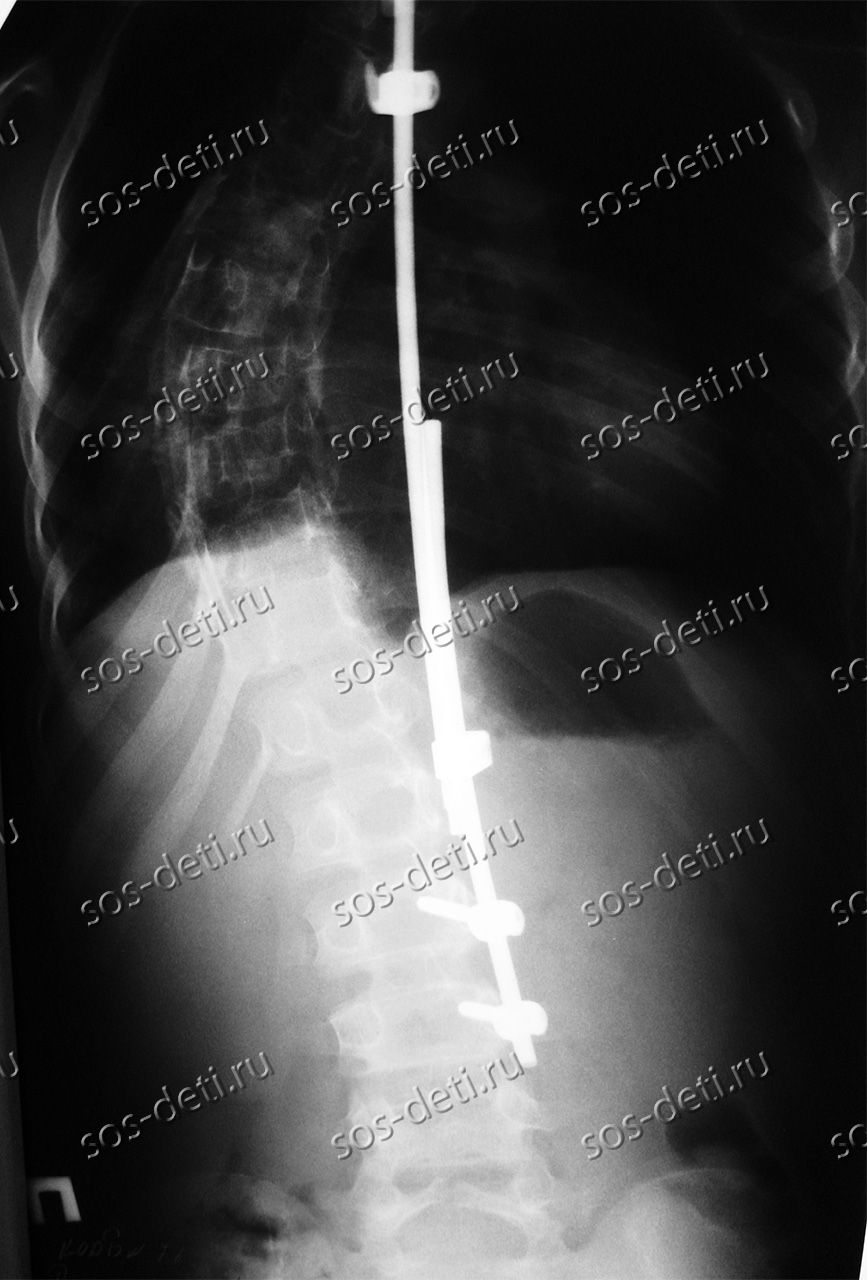

Патимат 14 лет, она из Ферзиковского района Калужской области. Её диагноз – ювенильный идиопатический правосторонний грудной сколиоз 4 степени, состояние после оперативного лечения, усталостный перелом стержня дистрактора. Впервые сколиоз выявлен в 4 года. С 2010 года наблюдается резкое прогрессирование. Первый этап оперативного лечения был проведен в 2011 году, была установлена металлоконструкция с использованием имплантатов Medtronic (США) педиатрического размера. В 2015 году была проведена операция этапной коррекции металлоконструкции. В настоящее время в связи с ростом подопечной необходимо провести завершающий этап лечения в Калужской областной детской больнице с установкой имплантатов стабилизации позвоночника Medtronic (США). Оплата имплантатов за счет бюджетных средств не производится. Стоимость базовой комплектации имплантатов и расходных материалов составляет 751 600 рублей.

Первичную операцию сделали в декабре 2011 года – пять лет назад. В 2016 году Патимат оперировали 2 раза – конструкция дала трещины, титан не смог сдержать прогрессирование болезни (у девочки педиатрическая модель имплантатов), да и позвоночник растет. Конструкция, которую установили пять лет назад уже не соответствует размеру позвоночника девочки и требует перемонтажа – замены на больший размер. Патимат не может долго ждать, конструкция может сломаться в любое время. Каждый раз ложиться под хирургический нож для поддерживающей коррекции – не выход из положения. Нужна новая операция.

Пять лет назад в мединституте им. Турнера врачи говорили, что до 18 лет не надо делать операцию. Но учитывая стремительную прогрессию, ждать было нельзя. Прогноз был однозначный: горб, непредсказуемое искривление позвоночника вплоть до спиралевидной формы и неврологические осложнения, вплоть до парализации. Конечно этого допустить было нельзя. Именно поэтому в Калужской областной детской больнице было принято решение оперировать девочку в раннем возрасте и ей установили имплантаты Medtronic (США) малых размеров.